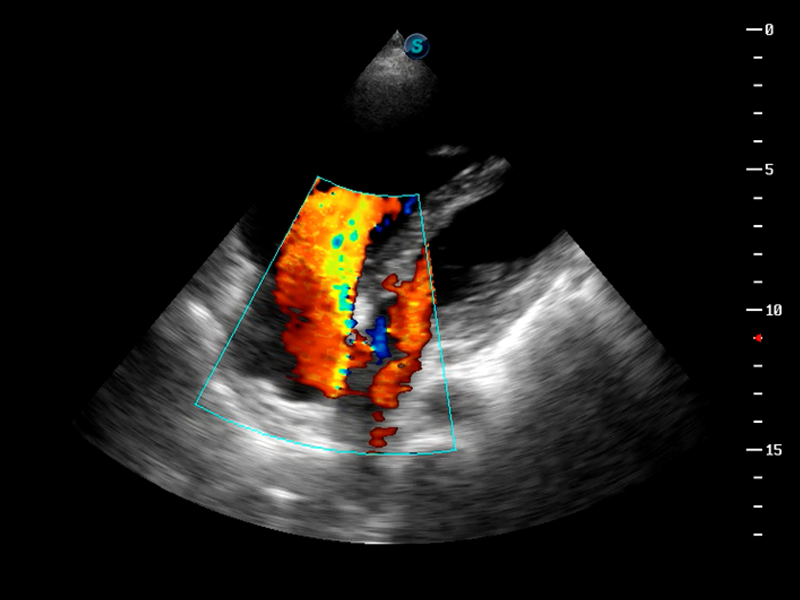

脉冲反相谐波成像

AutoC智能血流追踪